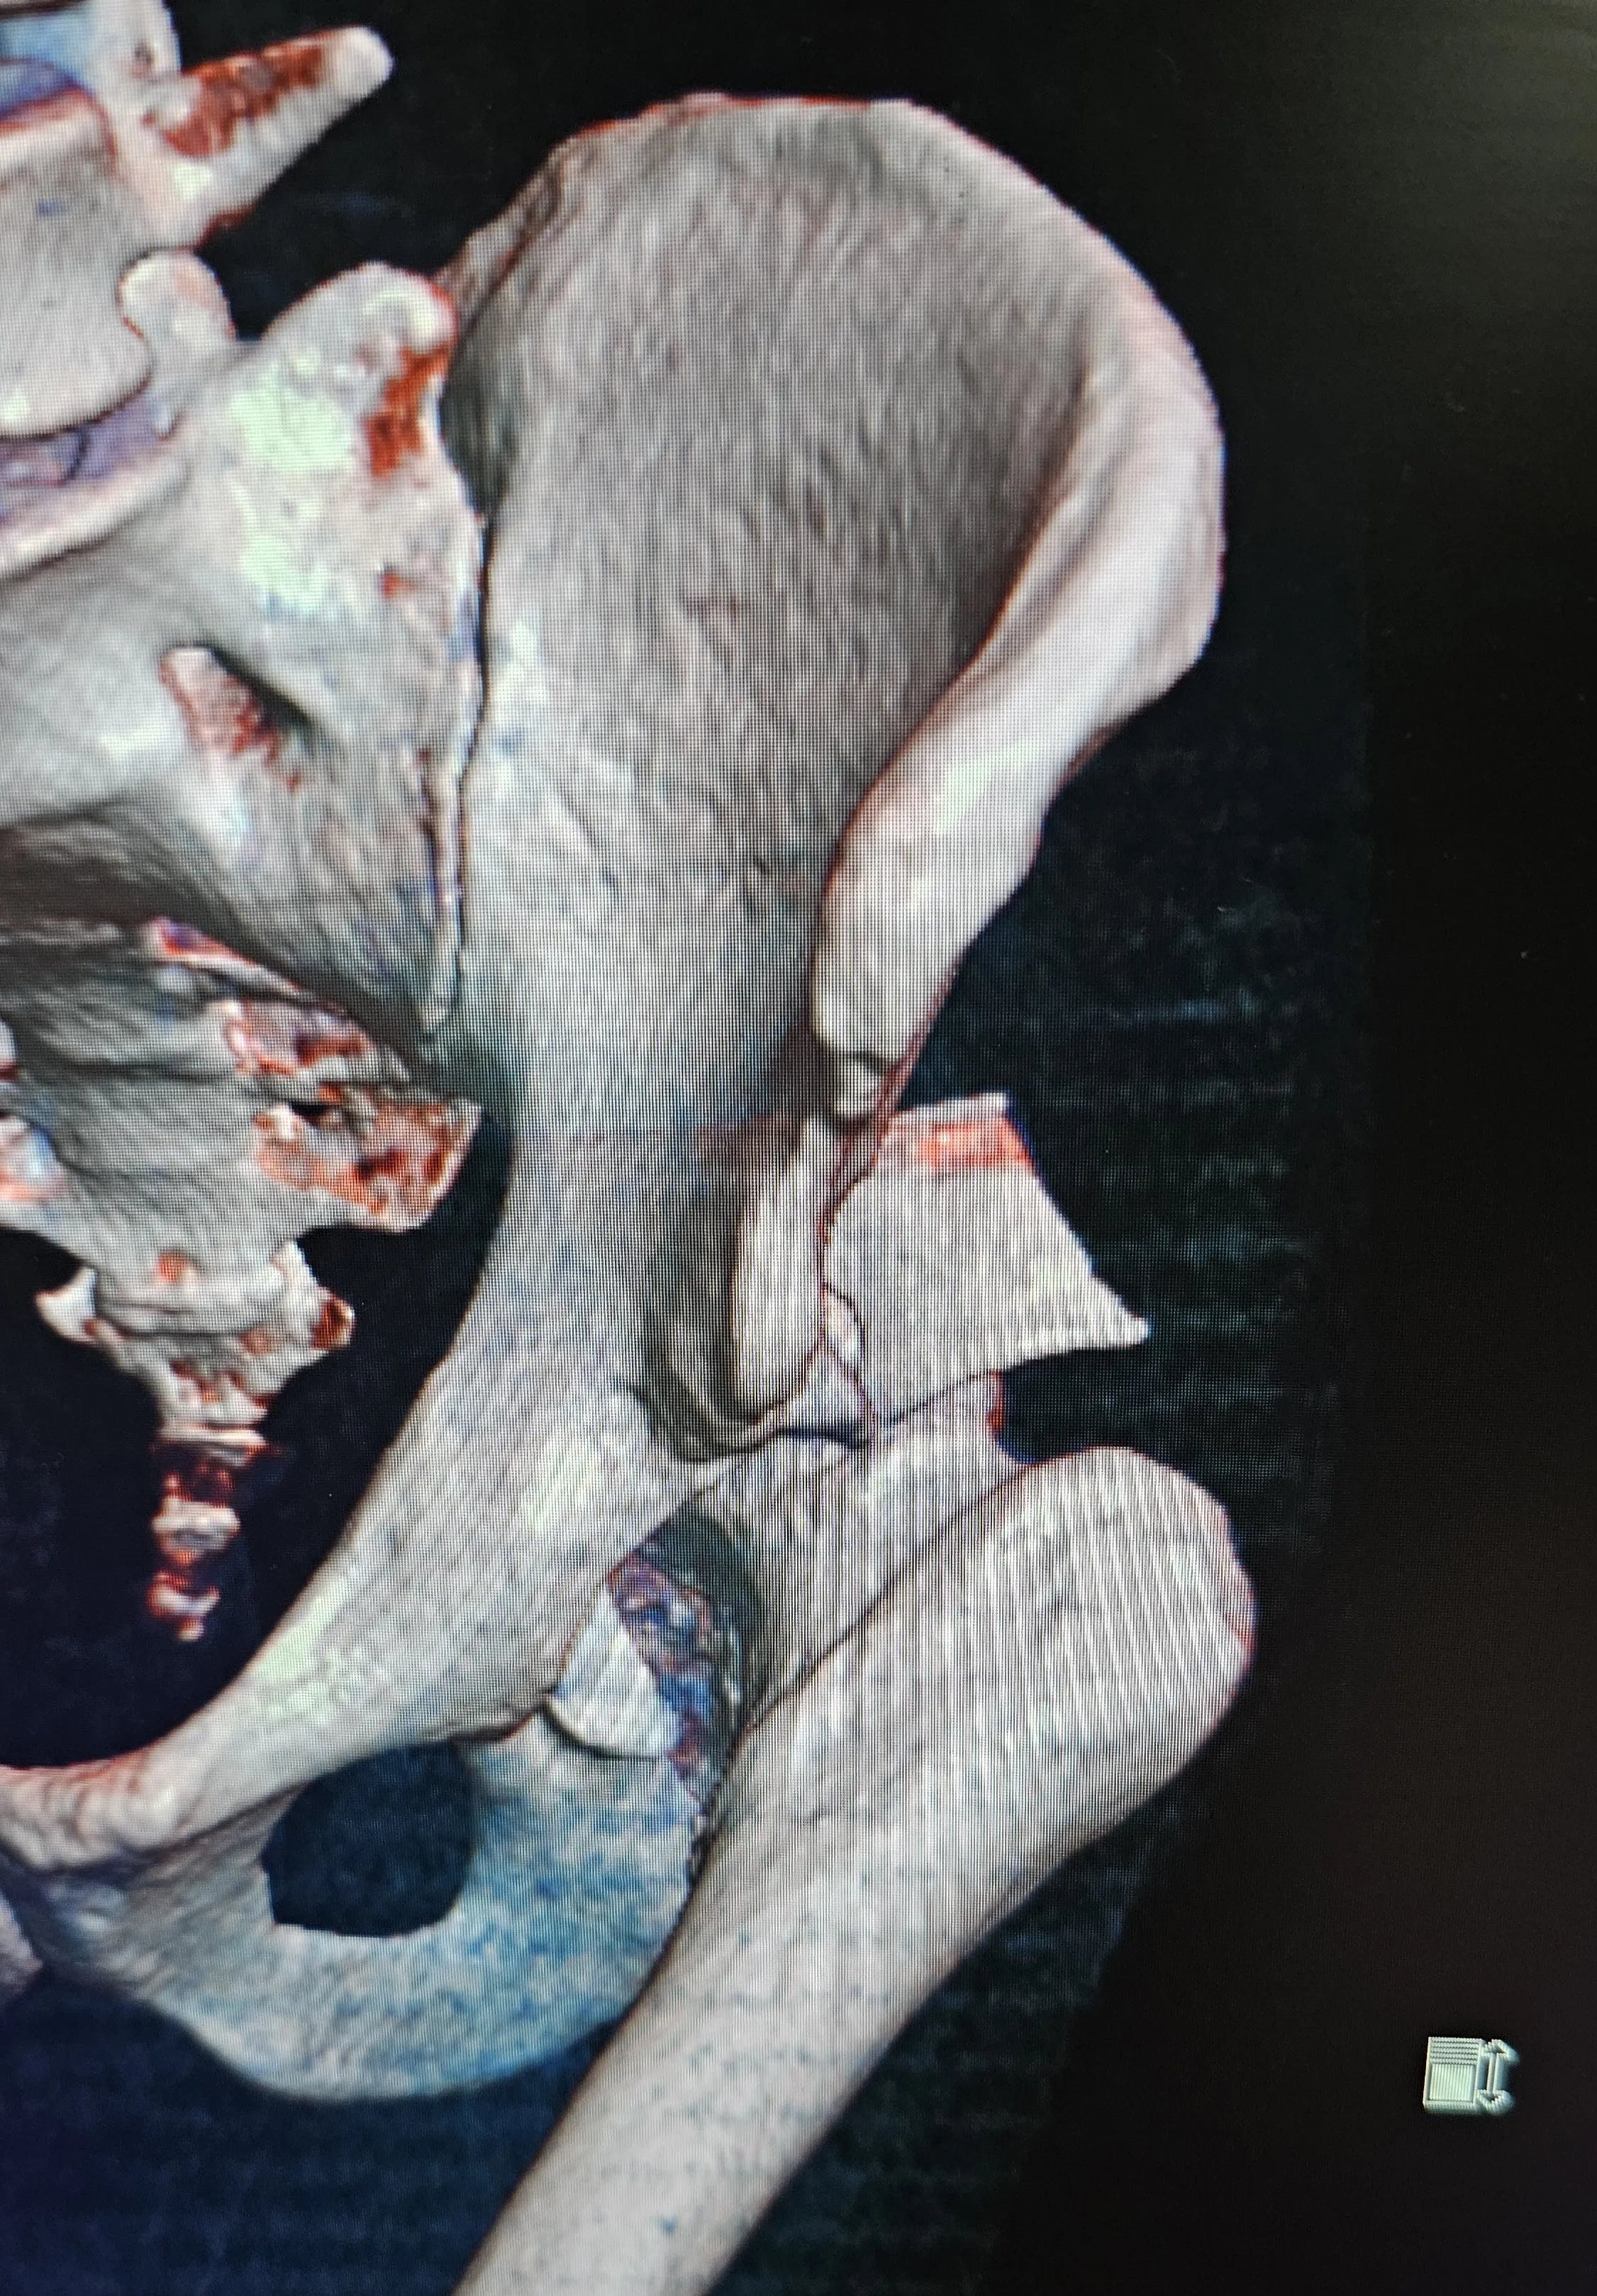

Fratura do Rebordo Posterior do Acetábulo com Luxação do Quadril

- Avaliação Inicial e Acesso Cirúrgico Otimizado: Aprenda a interpretar tomografias computadorizadas para identificar luxação do quadril e grandes fragmentos do rebordo posterior do acetábulo. Domine o acesso de Kocher-Langenbeck, utilizando pontos de referência como o ápice do trocânter maior, a espinha ilíaca póstero-superior e o eixo longo do fêmur.

- Identificação e Redução Precisa dos Fragmentos: Saiba como identificar os fragmentos inferior e superior do teto acetabular. Aprenda a limpar e descolar a articulação para melhor identificação dos parâmetros de redução, e reposicionar os fragmentos em seus locais anatômicos após a redução da luxação.

- Fixação Provisória e Moldagem da Placa: Domine a técnica de introdução do afastador inferior na incisura isquiática menor após descolamento cuidadoso. Realize a fixação provisória dos fragmentos com fios de Kirschner. Utilize alumínio para moldar um modelo da placa, que será usado para a confecção de um molde definitivo da placa de fixação.

- Fixação Definitiva com Múltiplas Placas: Aprenda a fixar a placa principal no ísquio, contornando todo o rebordo posterior, com parafusos direcionados para o teto acetabular. Utilize uma segunda placa no vértice do fragmento superior para fixação. Compreenda como a utilização dessas duas placas proporciona redução e estabilidade satisfatórias, eliminando a necessidade de placas em mola.